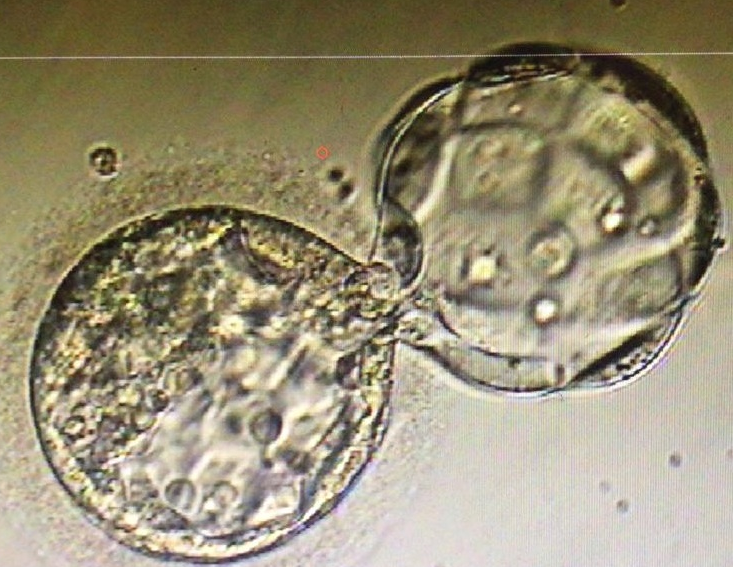

Human day 2 embryo generated in a SYNTHETIC PROTEIN-FREE (ART-7b) MEDIUM (fertilization up to day 2). Embryo transfer (n=3) was performed on day 2. The ART-7b medium has been phased out. This embryo is now a young man in his early twenties, one of a set of triplets (all boys). This was the first report of the successful generation of human embryos in a completely synthetic medium devoid of donor serum proteins. (Proc. XVI Ann. Sci Meeting Fertil Soc Australia, 2-4 Nov, 1997, Adelaide, Australia, p.34; Ali et al., Human Reprod 15:145, 2000).

Human day 3 embryo generated in PFM-11 SYNTHETIC PROTEIN-FREE MEDIUM from fertilization up to day 3. The ART-7b and PFM-11 media have been phased out. The SYNBIOS®embyro culture and handling media is an improved formulation over its predecessors, the ART-7b and PFM-11 synthetic protein-free media.